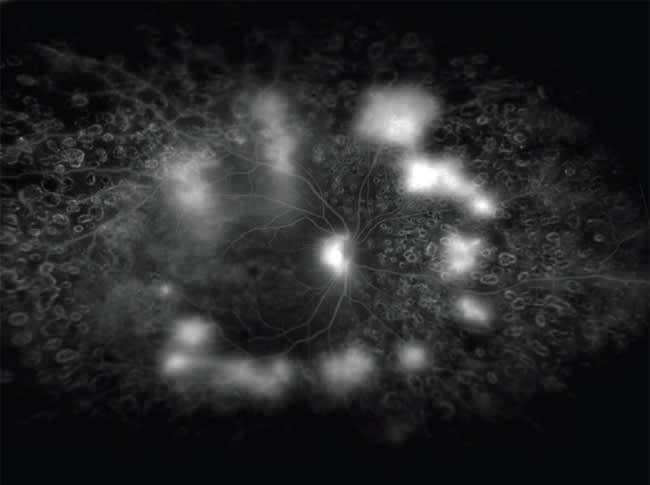

Figure 3. Stargardt disease with classic findings of “bull's eye” maculopathy, numerous pisciform flecks and a dark choroid.